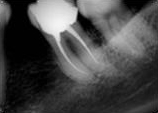

antes depois